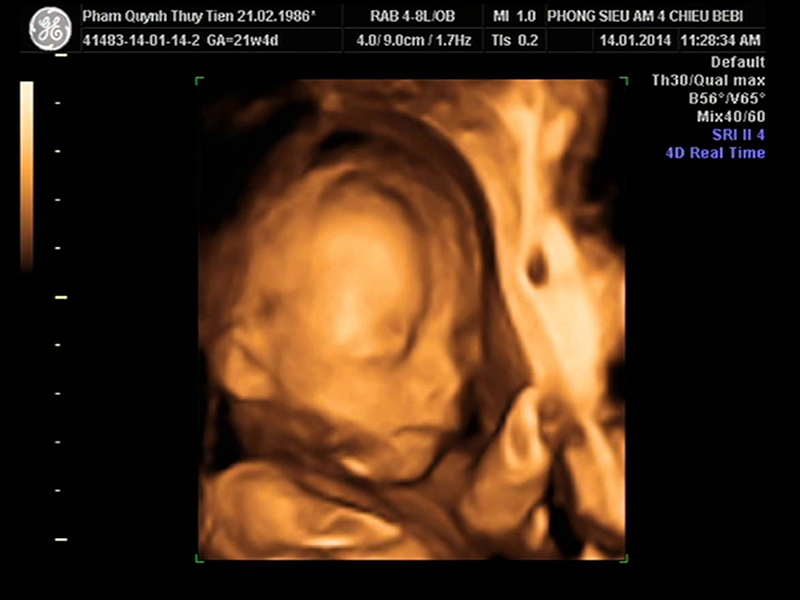

1. Thai nhi 22 tuần tuổi nặng bao nhiêu? Chỉ số thai 22 tuần

Đường kính lưỡng đỉnh (BPD): 50 – 62 mm

Chu vi vòng đầu (HC): 199 – 223 mm

Chiều dài xương đùi (FL): 37 – 44 mm

Chu vi vòng bụng (AC): 72 – 204 mm

Bé 22 tuần tuổi bắt đầu có hình dáng giống trẻ sơ sinh hơn khi môi, mí mắt và lông mày trở nên rõ nét. Trong giai đoạn này, các giác quan của bé phát triển từng ngày. Chồi vị giác đã hình thành trên lưỡi, và não bộ cùng dây thần kinh đã phát triển đủ để thai nhi cảm nhận được sự va chạm.